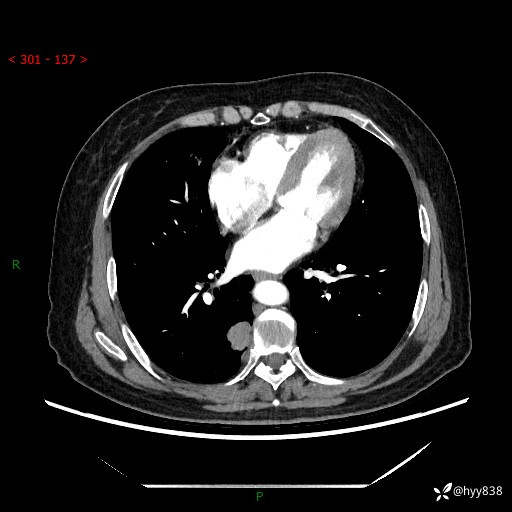

增强动脉期+静脉期

两期CT值:55Hu 53hu